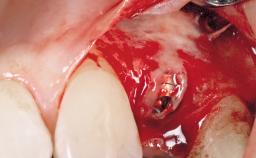

Immediate Flapless Placement of an Implant in a Maxillary Right Lateral Incisor Site

This 43-year-old male patient, a non-smoker, came to our practice because of a fracture of tooth 12 caused by a bicycle accident. Due to the combined para- and infrabony crown and root fracture, tooth extraction, and subsequent implant placement were suggested to the patient as the therapy of choice. The patient had high esthetic expectations with regard to the treatment outcome and asked for an immediate fixed provisional restoration. His individual esthetic risk profile summed up to a medium esthetic risk.

Placement Protocol Immediate implant placement

Socket Integrity Sufficient, with intact bone walls

Bone Volume Sufficient, with intact walls